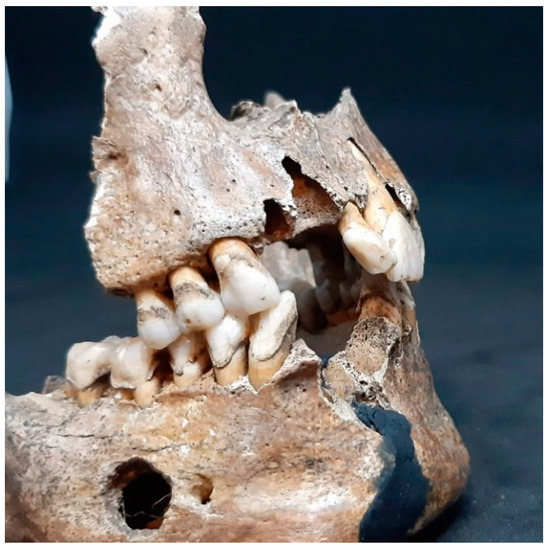

3.2. Inspection of the Jaws

3.2.1. The Maxilla

3.2.2. The Mandible

3.2.3. The Teeth

3.2.4. The Occlusion

3.2.5. The Mesiodens